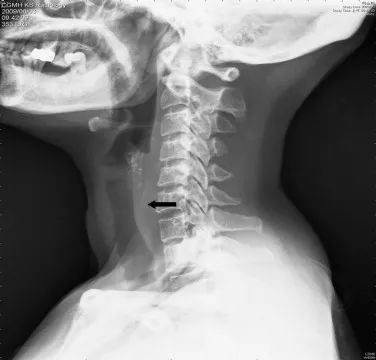

07 一个“鱼骨 混腺 ”的故事

《医学案例报告》(Case Reports in Medicine)上的一篇文章说,有医生在一名31岁妇女的甲状腺里发现了一根鱼骨。显然,在她吃东西的时候有一根鱼骨卡在了她的喉咙里,然后误入了她的甲状腺。

在检查过程中医生们费了很大一番功夫,因为鱼骨作为入侵人体的异物是比较难被发现的。每年世界各地频发的鱼刺伤人案例,足以提醒我们所有人在食用海鲜时多加注意。减少交谈,进食鱼类时尽量细致小心是我们保护好自己的重要方式。